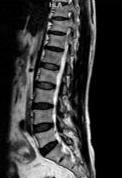

• 单侧双通道内镜与经皮椎间孔镜技术治疗极外侧型腰椎间盘突出症的临床疗效对比

摘要:目的 比较单侧双通道内镜(UBE)与经皮椎间孔镜下髓核摘除术(PTED)治疗极外侧型腰椎间盘突出症(FLLDH)的临床疗效。方法 回顾性分析2021年3月-2023年3月于该院进行治疗的FLLDH患者42例,根据手术方法不同,将患者分为UBE组(18例)和PTED组(24例)。记录并比较两组患者手术时间、术中透视次数、住院时间和围手术期并发症等指标。采用疼痛视觉模拟法(VAS)评估疼痛程度,Oswestry功能障碍指数(ODI)评估功能障碍情况,Macnab评分标准评估临床疗效。结果 UBE组手术时间为(95.56±20.94)min,较PTED组的(78.25±17.23)min长,术中出血量为(69.17±8.95)mL,较PTED组的(23.96±5.89)mL多,差异均有统计学意义(P < 0.05)。UBE组住院时间为(5.67±1.28)d,与PTED组的(5.33±1.05)d比较,差异无统计学意义(P > 0.05)。UBE组术中透视次数为(3.00±0.77)次,明显少于PTED组的(7.42±0.93)次,差异有统计学意义(P < 0.05)。两组患者术后VAS评分和ODI较术前明显降低,差异均有统计学意义(P < 0.05)。术后3 d,UBE组腿痛VAS评分为(3.28±0.58)分及ODI为(41.17±4.30)%,明显低于PTED组的(4.13±0.74)分及(45.50±3.91)%,差异均有统计学意义(P < 0.05),但两组患者术后3个月和1年的VAS评分及ODI比较,差异均无统计学意义(P > 0.05)。两组患者优良率比较,差异无统计学意义(88.9%和87.5%,P = 0.563)。PTED组围手术期出现神经损伤2例,UBE组无神经损伤出现,两组均无感染、复发和大出血等严重并发症发生。结论 PTED与UBE两种手术方式治疗FLLDH均安全和有效。但UBE术中透视次数少,镜下视野更加清晰,神经损伤风险更小。